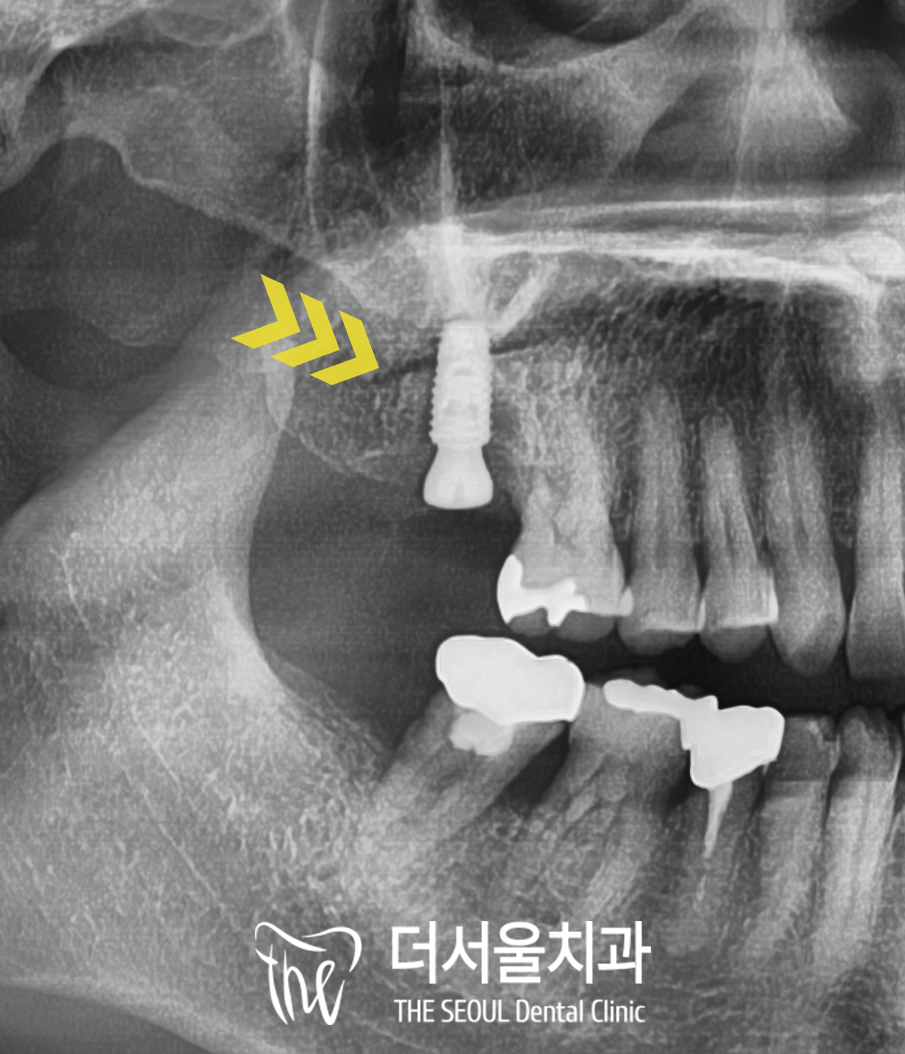

그다음 말씀드린 sinus lift를 동반한

뼈이식을 진행하고

그 자리로 알맞은 사이즈의

픽스처도 안전하게 심었습니다.

3개월 정도 시간이 지나고 나면

치조골과 단단하게 유착되는데요,

모란역 치과 에서는

픽스처의 고정력을 측정하는

isq를 이용하여 수치를 확인하고

평균 75 이상의 안정 수치가 나오면

그 위로 보철을 올려드립니다.

보철은 지르코니아라는

심미성과 강도가 강한

좋은 재료를 사용하였으며

그 사이로 맞춤형 어버트먼트를

제작하여 연결해 주었기에

디지털 임플란트와 보철이

틈이나 굴곡 없이

매끈하게 잘 연결된 것을 확인할 수 있습니다.